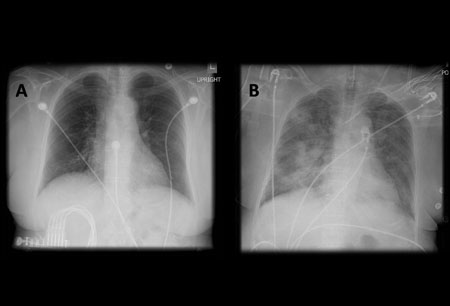

[Figure caption and citation for the preceding image starts]: A. Radiografia torácica portátil ortostática antes da aspiração; B. Radiografia torácica 1 hora após a aspiração, mostrando infiltrados alveolares difusos bilaterais, piores nas bases do lado direitoDo acervo de Dr. Henri Colt [Citation ends].